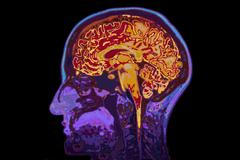

Mozek je jeden z nejzáhadnějších orgánů lidského těla. Váží zhruba 1300 až 1400 gramů, což představuje asi dvě procenta lidské váhy. Spotřebuje asi pětinu veškeré energie, které tělo člověka potřebuje a obsahuje mezi 50 až 100 miliardami neuronů. Poznáte na obrázku všechny jeho důležité části? Zkuste si náš kvíz.